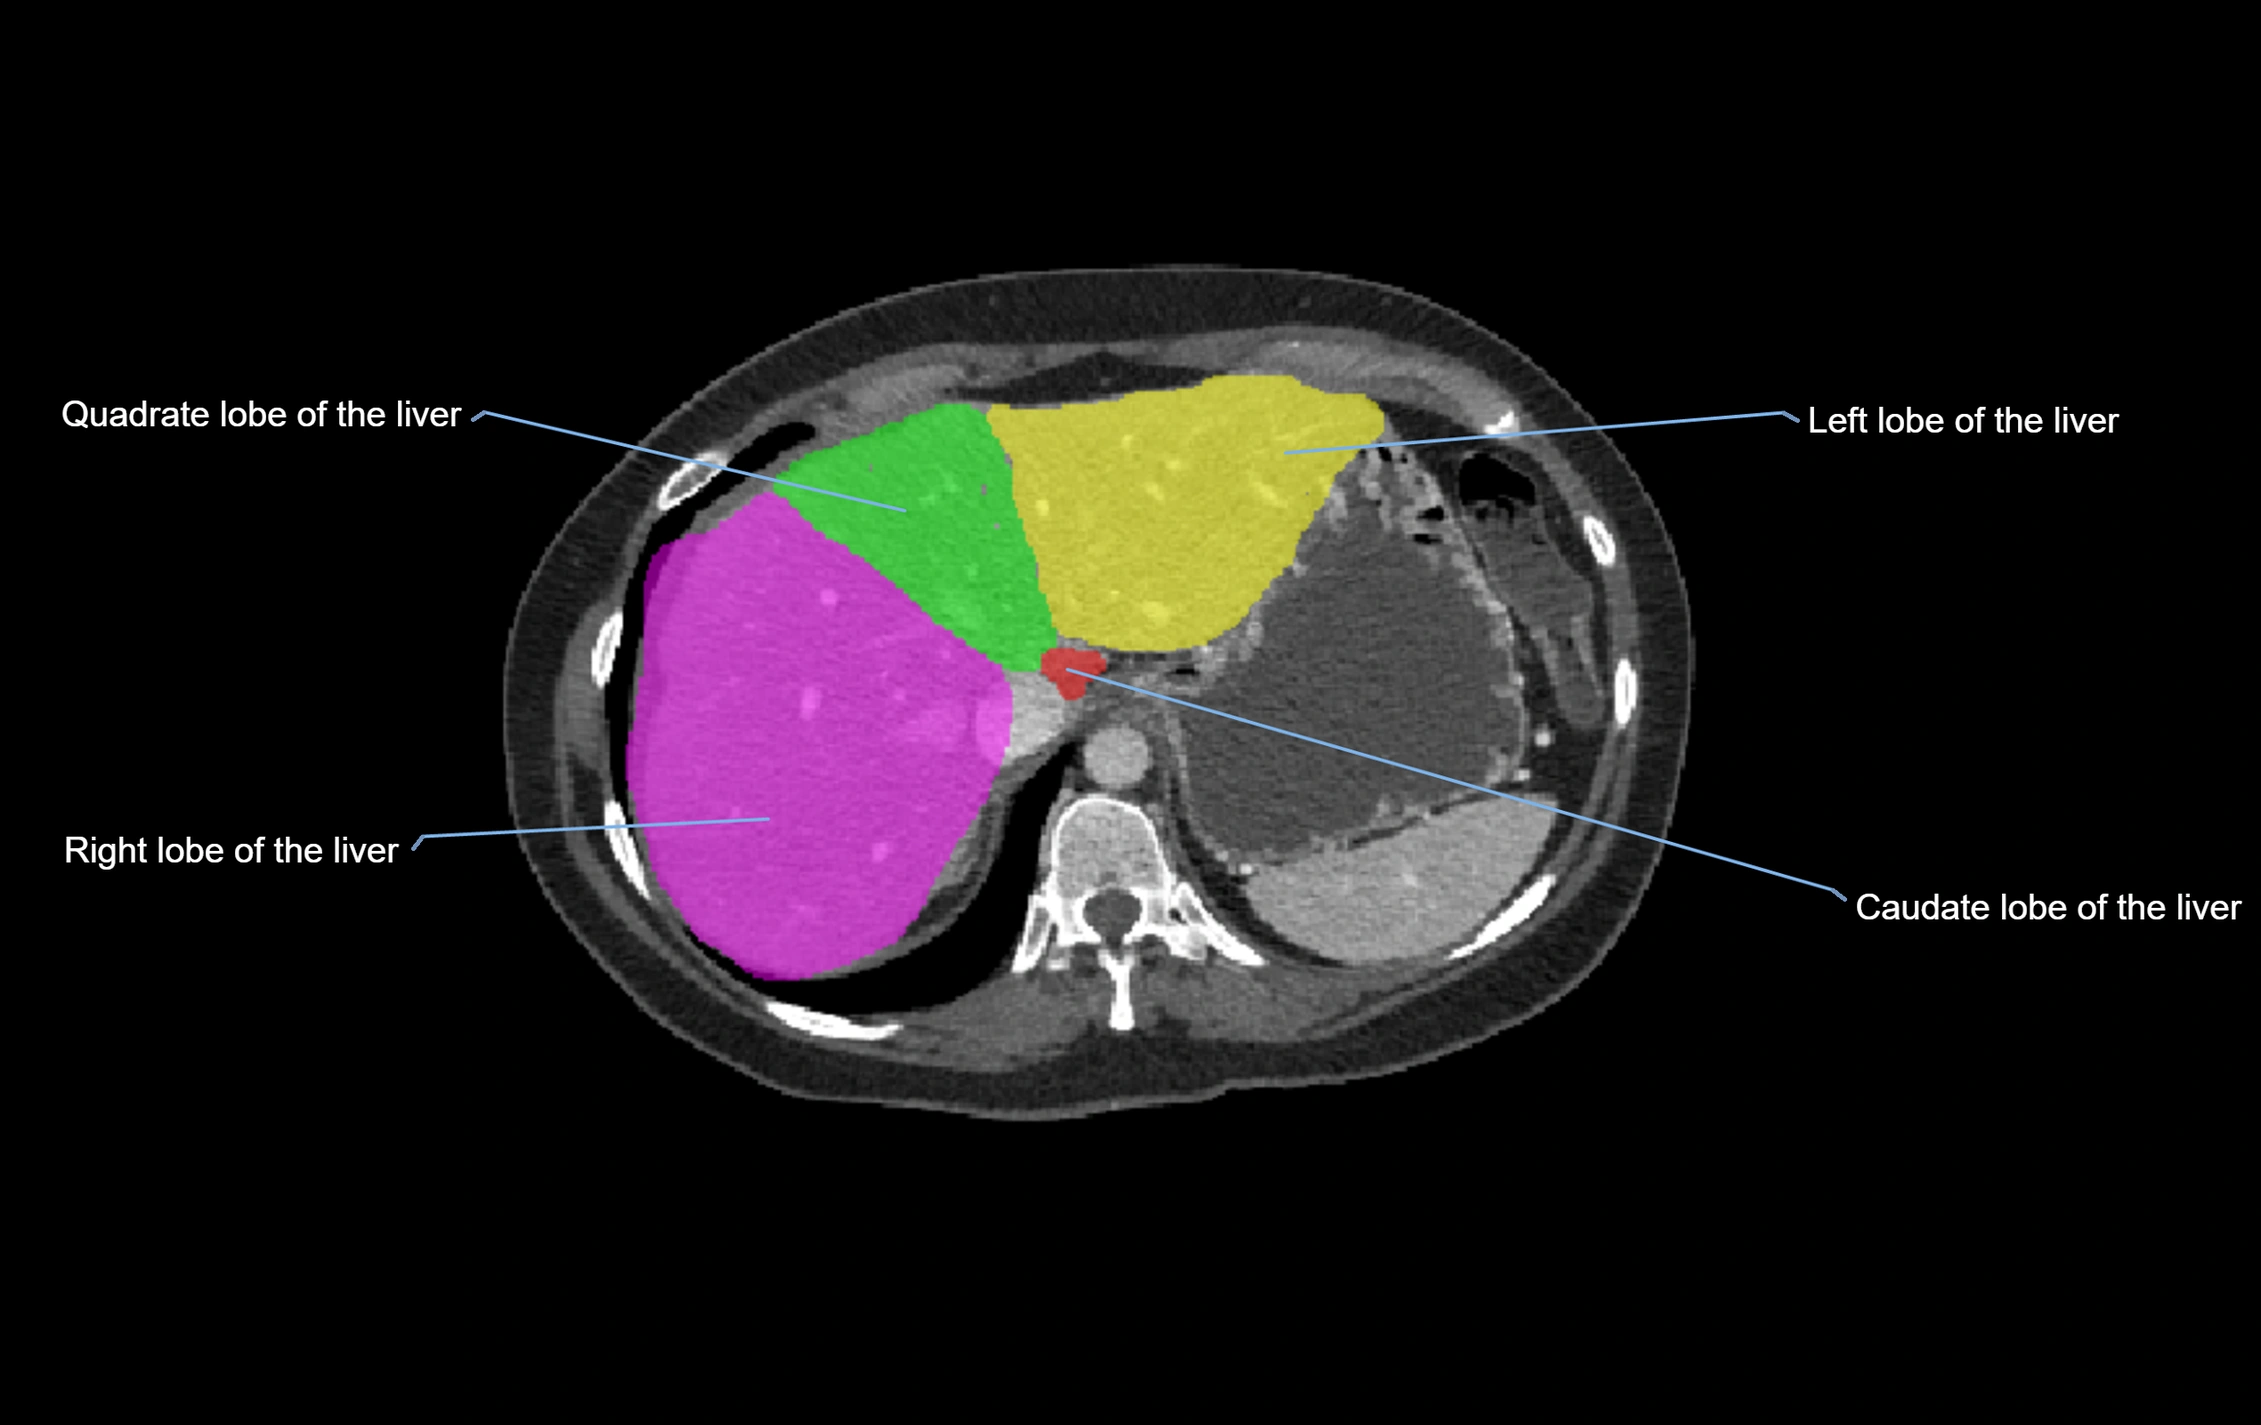

CT Appearance

CT Pre-Contrast:

• Caudate lobe appears as a soft-tissue density, isodense to the rest of the liver

• Enlargement may be appreciated in cirrhosis or Budd–Chiari syndrome

CT Post-Contrast:

• Homogeneous enhancement in the portal venous phase, similar to rest of liver

• Independent venous drainage into the IVC may be visualized

• Lesions follow characteristic CT enhancement patterns (HCC: arterial hyperenhancement with washout; hemangiomas: peripheral nodular enhancement with centripetal fill-in)

CT Venous Phase (functional significance):

• Caudate lobe often enhances relatively more than other lobes in Budd–Chiari syndrome, due to preserved venous outflow

CT Image

image